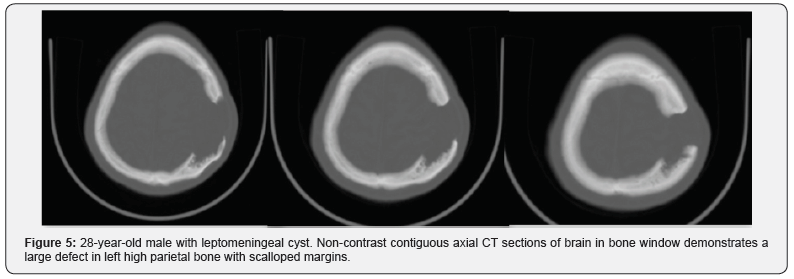

A 28-year-old male presenting with a gradually increasing scalp swelling in the left parietal region over a long period and seizures. The patient was conscious. On physical examination, there was a cystic swelling over the left parietal prominence. The swelling was compressible but non-tender and non-pulsatile. There was a history of head injury during infancy (Figure 1-5).

A non-contrast enhanced head computed tomography (CT) examination was performed on a multidetector CT (Lightspeed ultra, GE Medical Systems) and demonstrated a large calvarial defect in the left parietal region with irregular and beveled margins. An adjacent CSF density cystic lesion of size 42x41mm noted in the left high parietal lobe. The cyst was seen communicating with the subarachnoid space and also seen extending though the calvarial defect. Mild widening of sulcal spaces and hypodense areas also noted in the surrounding brain parenchyma due to encephalomalacia. The cystic lesion was seen closely abutting the left lateral ventricle with focal dilatation of the ventricle. But there was no communication of the cyst with the ventricle. Corrective surgery was done. The intraoperative and postoperative period was uneventful.